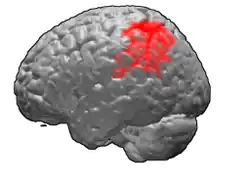

Brodmann area 40 (BA40) is part of the parietal cortex in the human brain. The inferior part of BA40 is in the area of the supramarginal gyrus, which lies at the posterior end of the lateral fissure, in the inferior lateral part of the parietal lobe.

Lateral surface of left cerebral hemisphere, viewed from above.